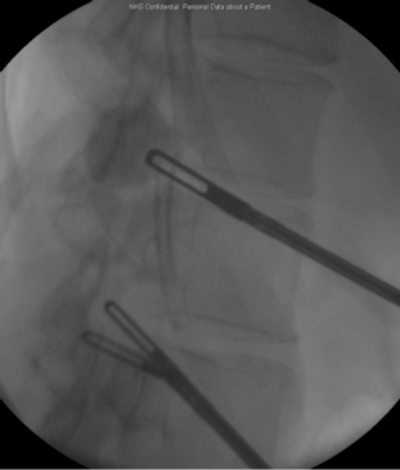

The patient underwent a laparoscopic nephrolithotomy. A right-sided four-port transperitoneal approach was used. The upper pole was extremely stuck and scarred and identifying the stone was very prolonged and difficult despite intraoperative fluoroscopy.

Intraoperative fluoroscopy used to identify the stone.